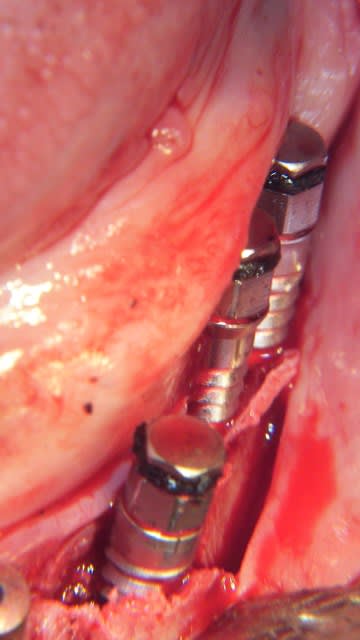

Un exemple de splitting sectoriel au maxillaire sup avec :

- piezo,

- osteotome,

- implant Astra osseospeed,

- comblement par mélange os autogène et BioOss,

- recouvrement par membrane BioGide + conjonctif palatin.

La suite dans quelques mois. ;-))